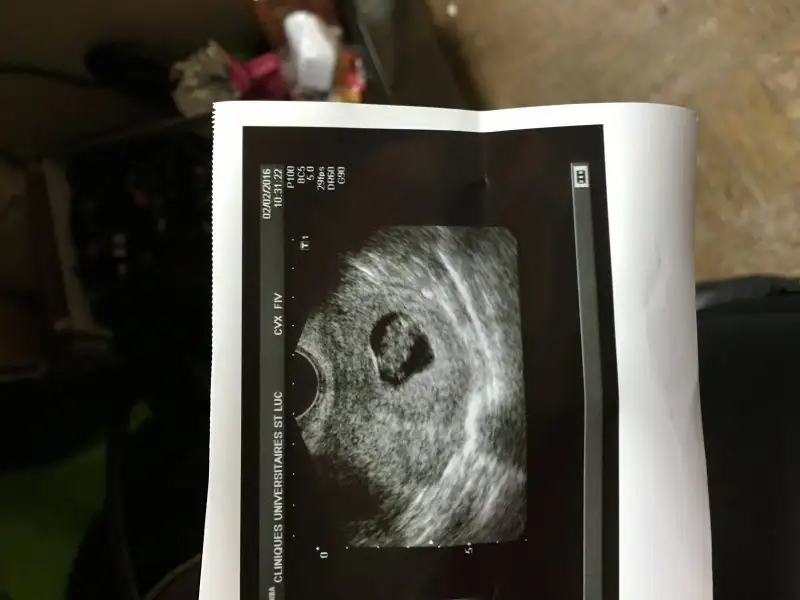

Ramzi Teorisi ve cinsiyet tahmini ( tutma olasılığı %85 miş )

E hadi benim çirkine de bakıverin o zaman teyzeleri.:) 7 haftalık vaginal usg. Üstteki bebek, altta yolk sac.